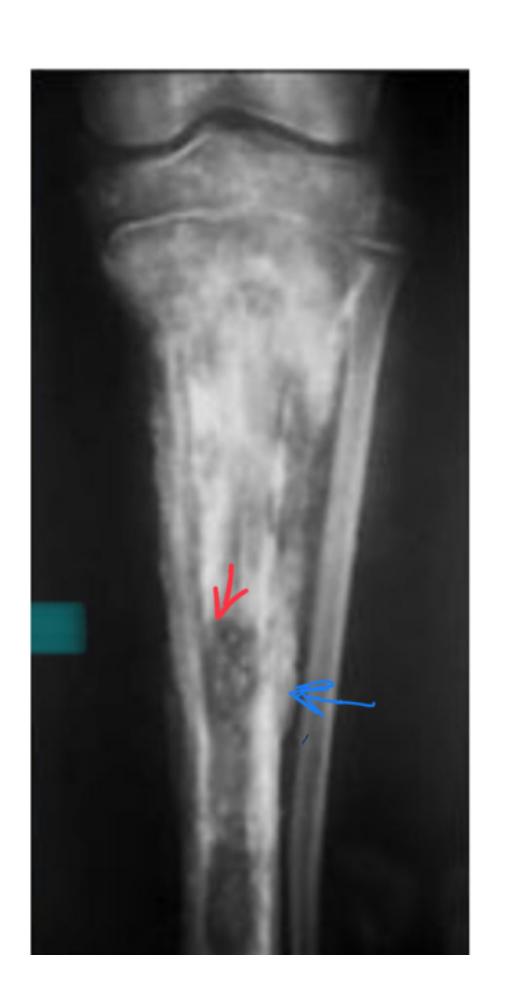

What anatomical structure is indicated by the blue arrow in a patient with chronic osteomyelitis?

- a. Involucrum

16- The blue arrow show?

A. Involucrum

What are the characteristic findings and diagnosis for a 7-year-old with painful swollen lower thigh and recurrent fever?

Q1: Abnormal x-ray findings:

- Cavitation

- Periosteal reaction

- Involucrum

- Sequestration

Q2: Diagnosis:

- Chronic osteomyelitis